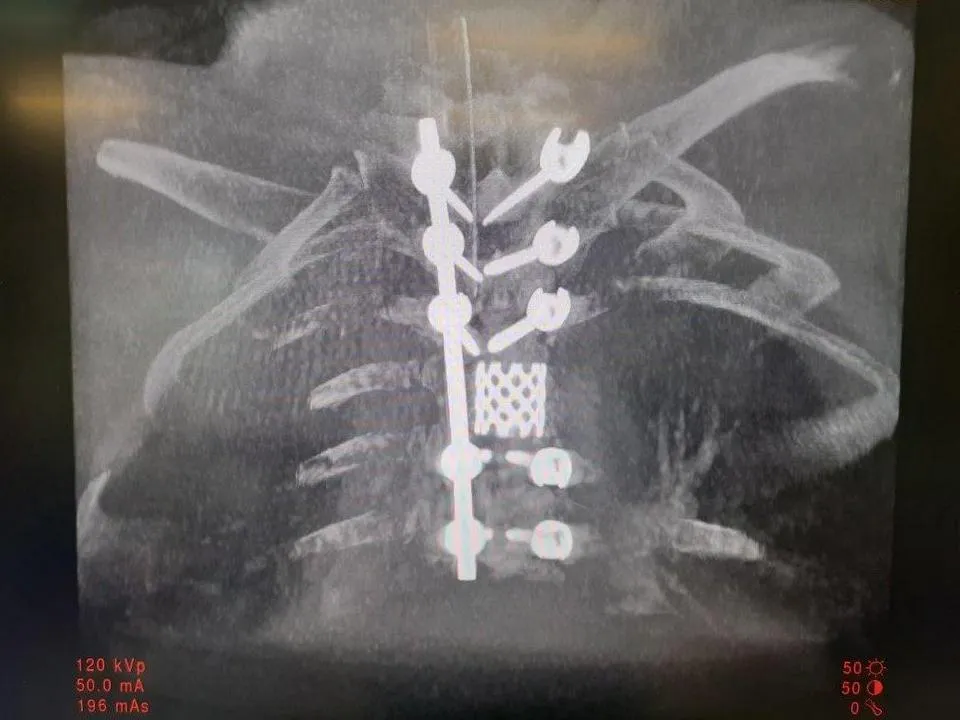

Нейрохирурги спасли от паралича трех пациентов с травмой после неудачного заплыва

Мытищинские врачи помогли трем пациентам, которые получили травмы при нырянии. Неосторожность на отдыхе проявили двое мужчин и одна женщина.

В разных местах на мелководье один из пациентов травмировал шейный отдел позвоночника, второй — грудной отдел с множественными переломами позвонков. У женщины была травмирована шея, парализованы ноги и обездвижена рука.

В Министерстве здравоохранения Московской области пояснили, что компрессионные переломы шейного отдела позвоночника грозят тяжелой инвалидностью. Они могут привести к параличу, нарушениям дыхания, а также мочеиспускания и опорожнения кишечника. Чтобы избежать осложнений, нужно незамедлительно обращаться к врачу за помощью.

Всем пациентам стало лучше. У женщины пропал паралич ног. Парез в руке уменьшился, при этом врачи отмечают, что он обратим. Это нарушение проявляется, как мышечная слабость. Пациентку после выписки направили на раннюю реабилитацию.

Мужчины после завершения послеоперационного периода уехали домой и перешли под наблюдение врача из поликлиники.